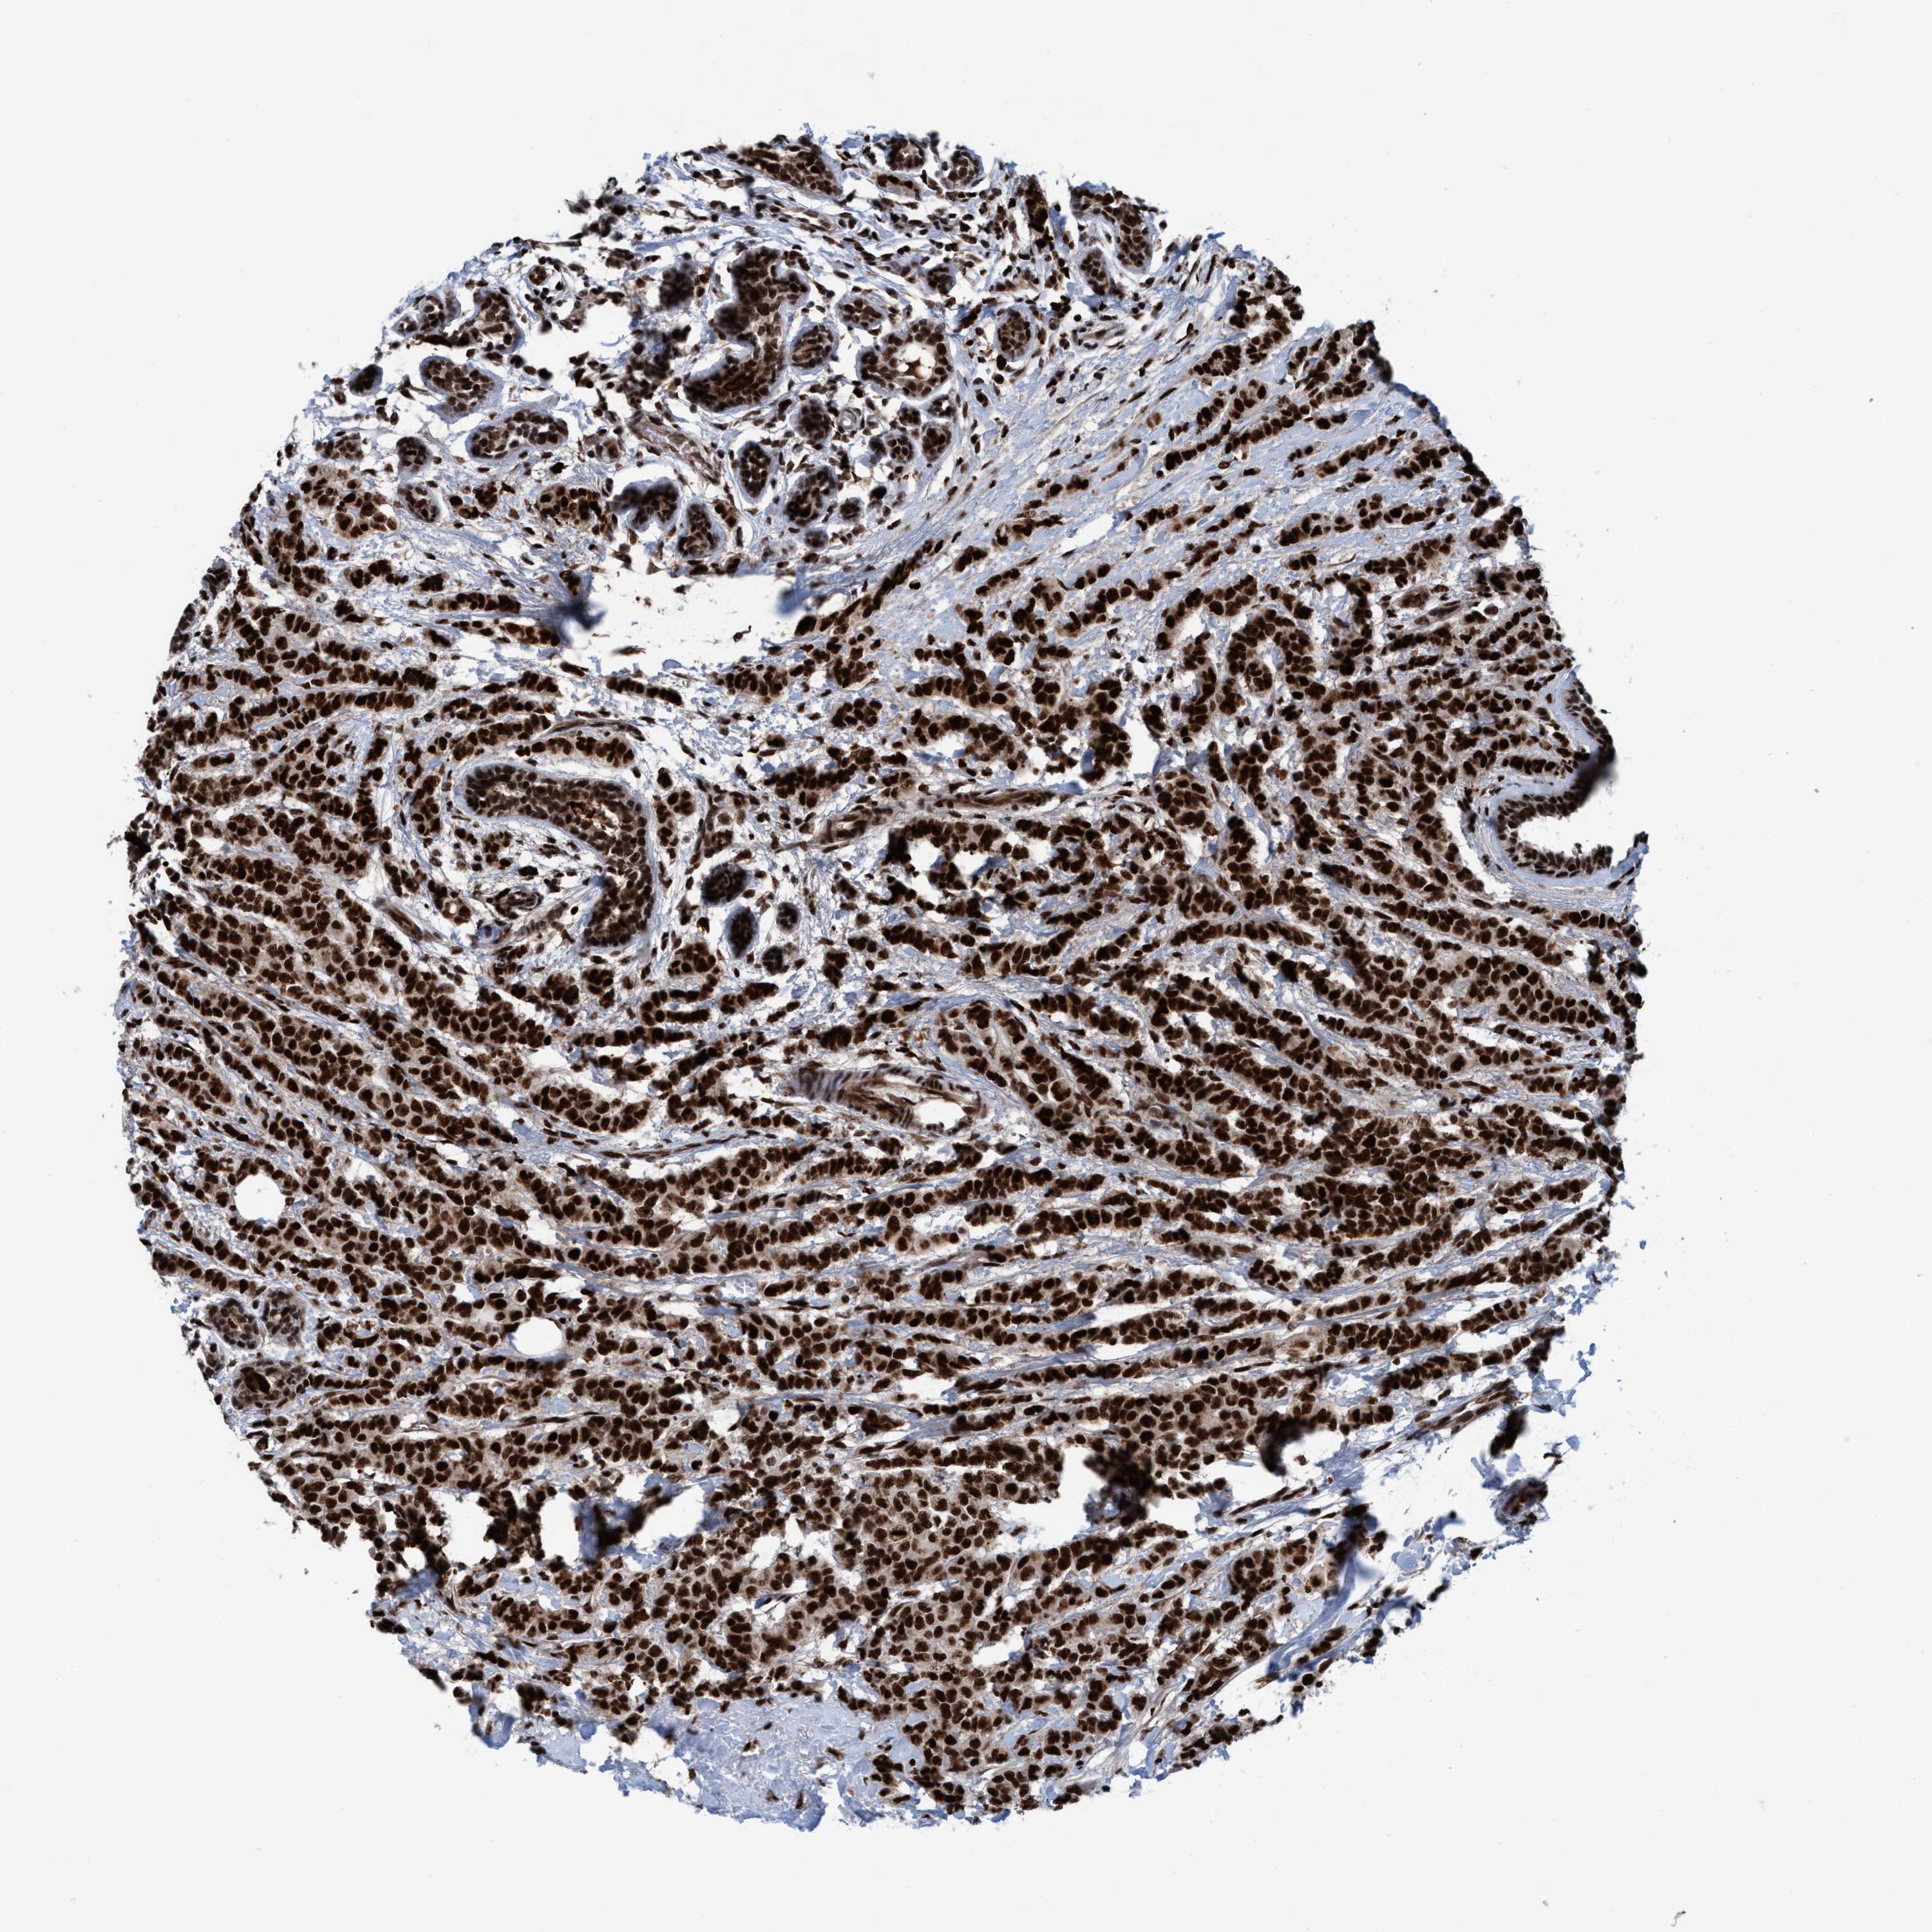

CANCER BREAST CANCER Show tissue menu

BRCA TCGA BRCA VALIDATION PROTEIN EXPRESSION

Breast cancer

Human cancer

Breast invasive carcinoma

TOPBP1 is not prognostic in Breast Invasive Carcinoma (TCGA)

Average pTPM 15.3

Number of samples 1022